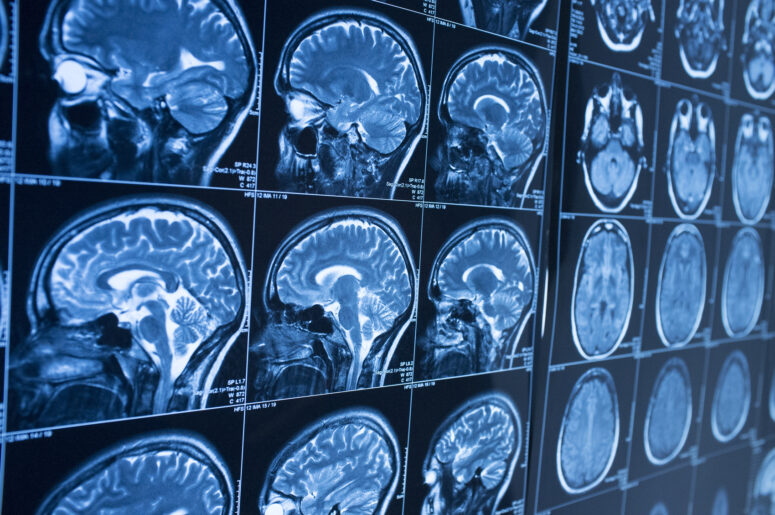

A TBI (traumatic brain injury) is a severe injury to the brain. It is defined by major damage to a person’s brain that can result in decline in memory, cognitive function and neurological operations. Severe TBIs can substantially reduce the future well-being of the victim and even leave them dependent on outside care and machines. As such, many doctors are devoted to finding ways to treat victims of TBIs and to help them regain full function of their brains.

One clinical trial studied the effectiveness of progesterone as a treatment for victims of severe TBIs. The clinical trial included about 1,100 people divided equally into test and control groups. Progesterone is widely associated with birth control, as a hormone that helps to prevent pregnancies. But it has also been shown in animal trials to inhibit inflammation of cytokines, prevents of excitotoxicity, reduction of apoptosis, and other benefits.